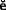

A loose retainer (Fig. 32-19) may not be easily perceived by the patient, especially if it is part of a fixed prosthesis supported by several abutment teeth. The patient may have noticed a bad taste or smell rather than detecting movement.

Fig. 32-19 A, Severe tooth destruction may result when a loose retainer goes undetected. B, Looseness of one retainer can occasionally be observed directly (arrow) when force is exerted in an occlusal direction. C, Water is then applied to the cervical area, and the diagnosis is confirmed if bubbles appear when pressure is exerted (D).